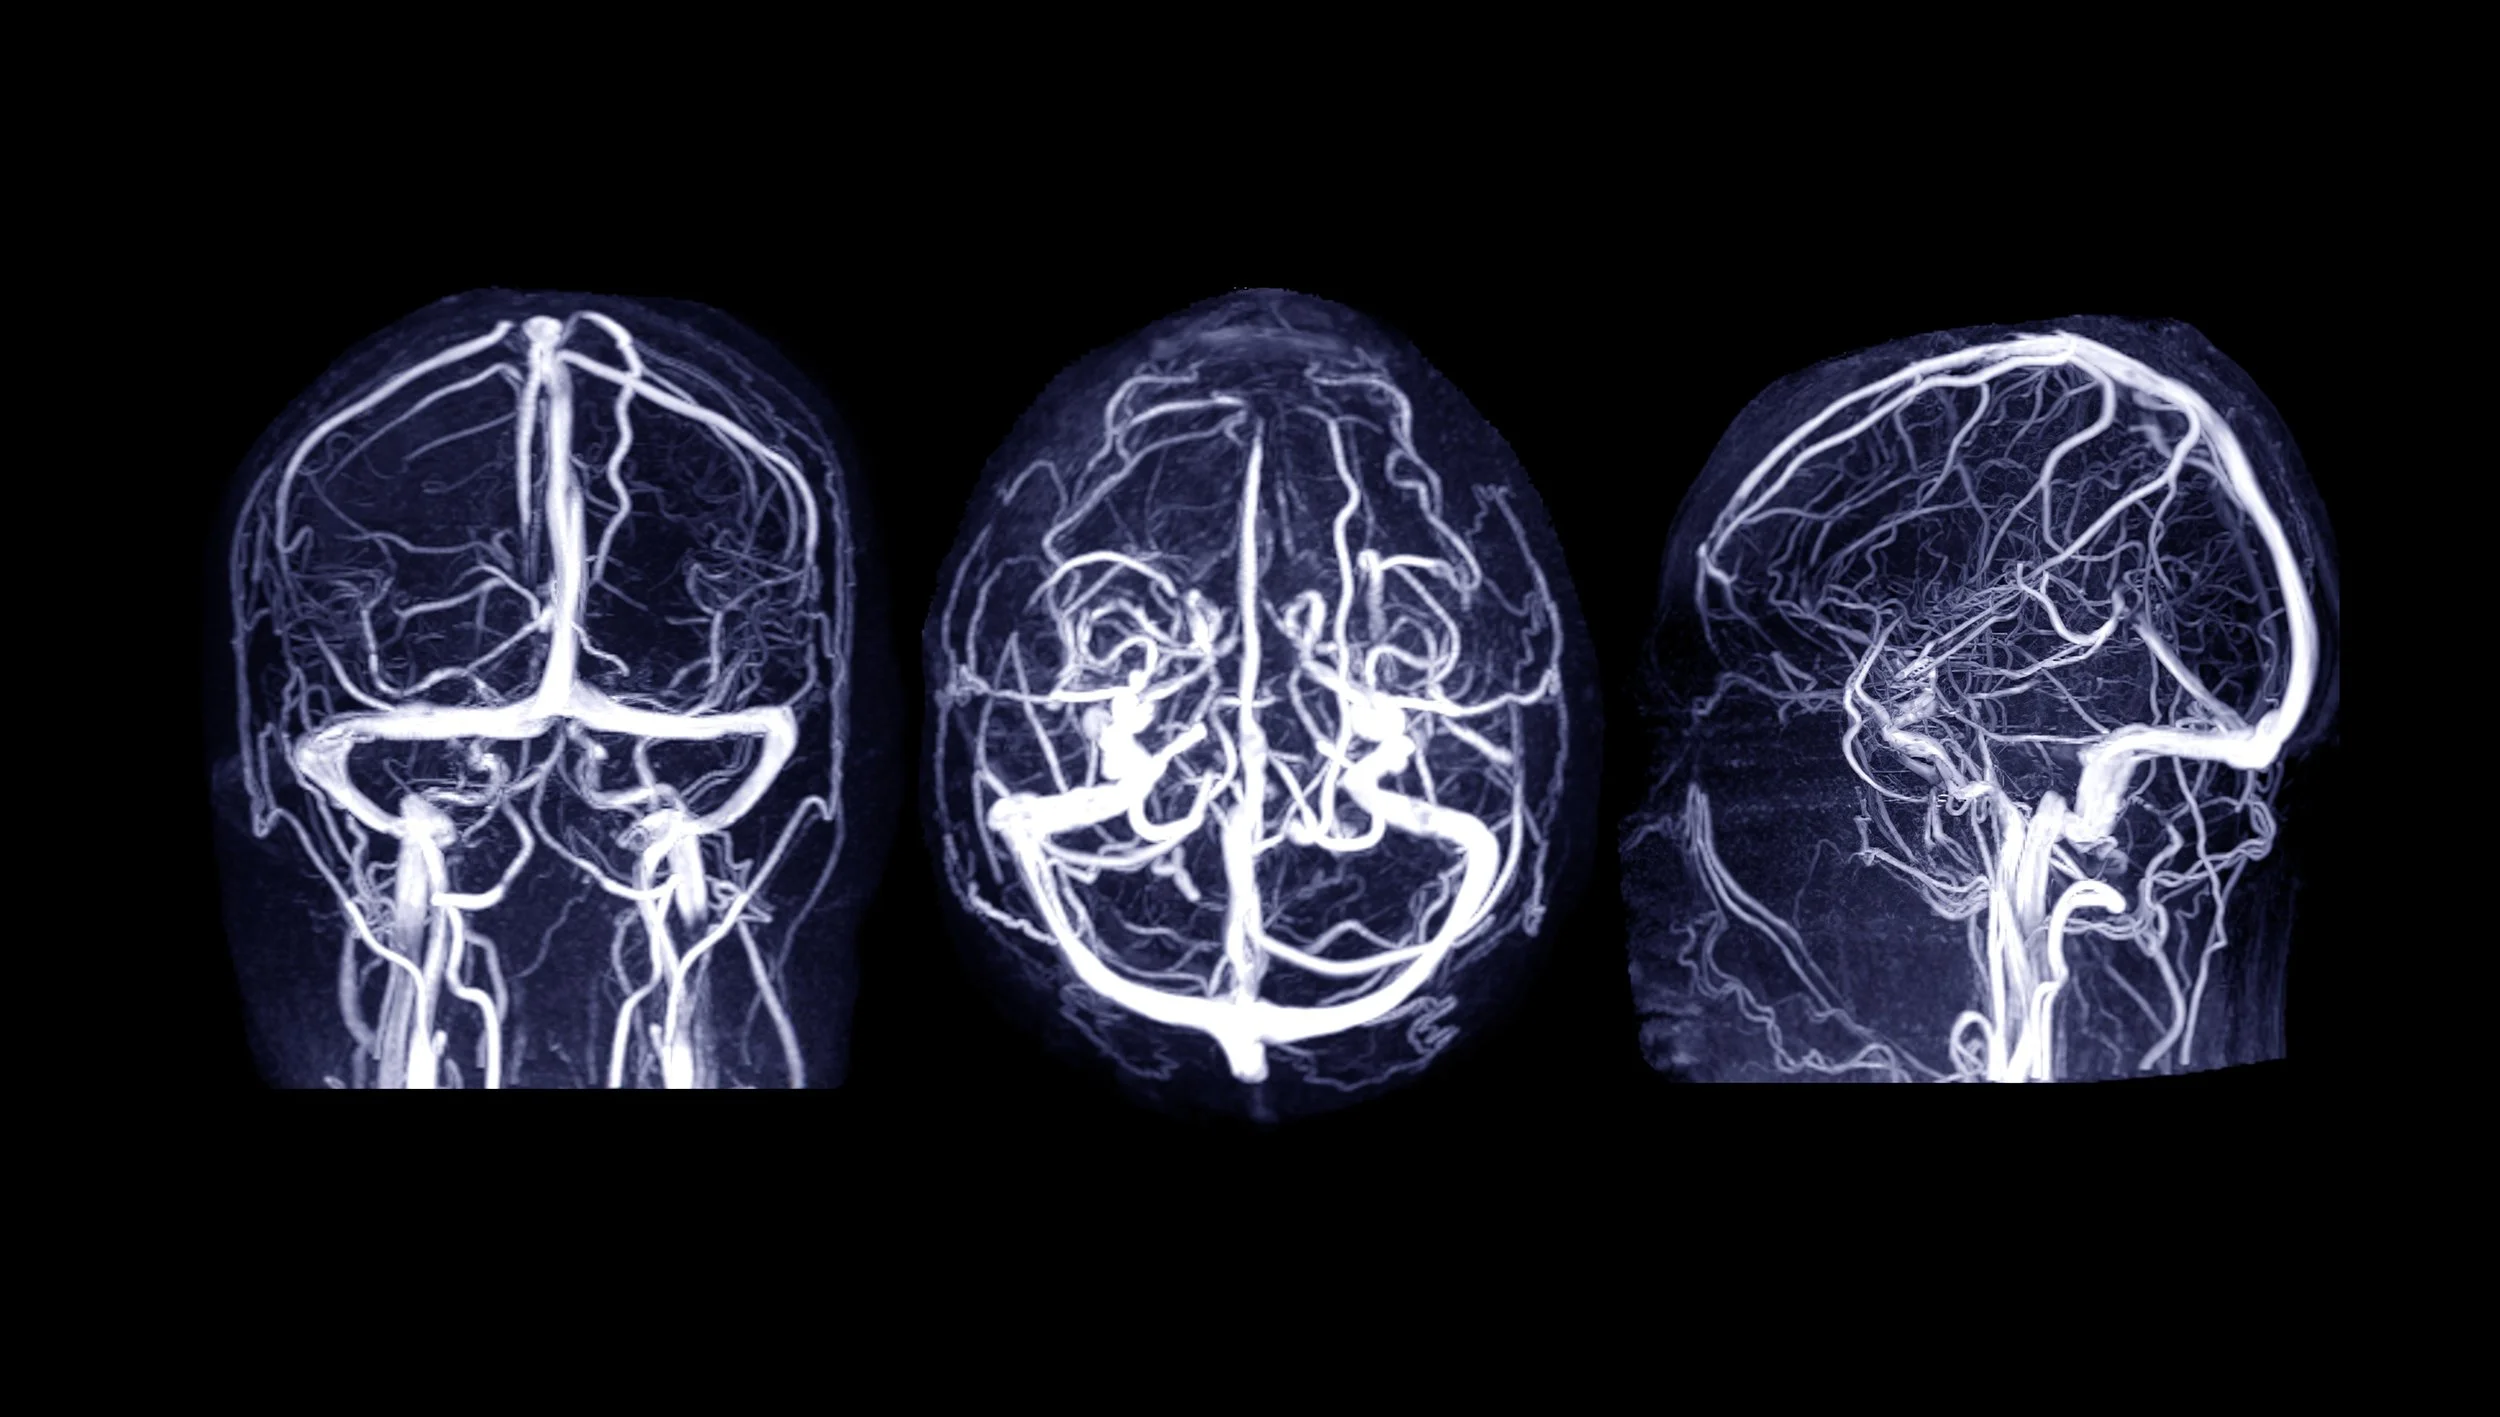

– VBI strokes are extremely rare, affecting between 2 and 3 cents per 100'000.

– These types of stroke happen at the frequency whether the patient has seen a doctor of chiropractic or medical doctor prior to the stroke. Leading the researcher to conclude that early VBI strokes manifest as routine neck pain and headache without any stroke related neurological signs yet, with patient seeking care from a variety of providers during the latent period